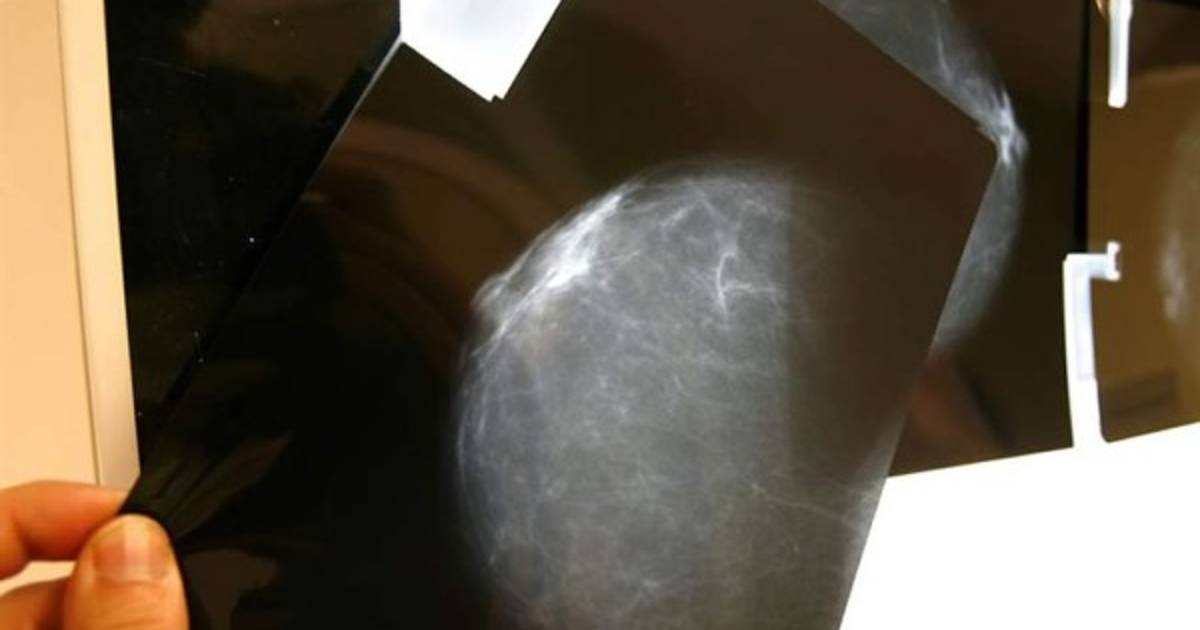

En el video, se muestra el pecho de un hombre que sirve para mostrar cómo hay que hacer un autoexamen mamario. Mira el video.

En poco más de un minuto, el pecho de un hombre sirve para mostrar cómo hay que hacer un autoexamen mamario e indicar qué hay que hacer si se encuentran anomalías.